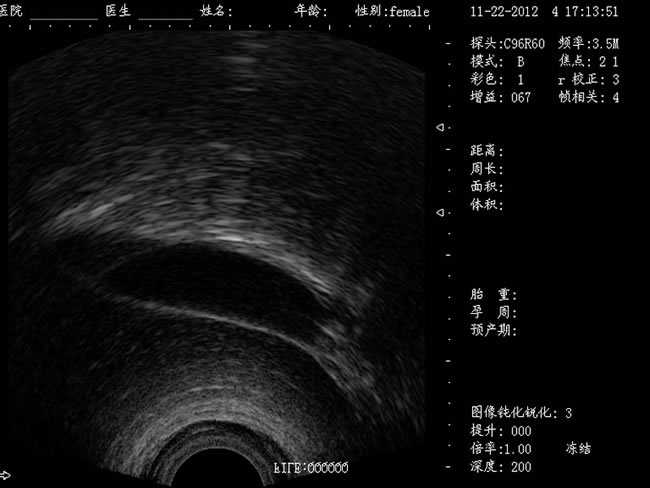

定位精確 手術效率高:實時動態頻率掃描等全數字超聲成像技術、生成精確的圖像引導手術器械迅速到大手術位置,避免損傷子宮內膜和子宮穿孔的現象,即減輕了患者的痛苦又極大提高了手術效率。

CXA10R/6.5MHz 腔內探頭

選配:CXA60R/3.5MHz 凸陣探頭

隨著醫療技術水平的提高,目前婦產科手術中所應用的相關設備也有了加大的改進。尤其是在人工流產手術中,將B超婦產科手術監視儀應用到手術過程中,彌補傳統手術中所采用設備的不足之處,減輕手術中患者的疼痛感覺,使得手術順利的完成。這種儀器相比于傳統的儀器來說,其在操作上更為方便和簡單,能夠對妊娠反應有很好的療效。